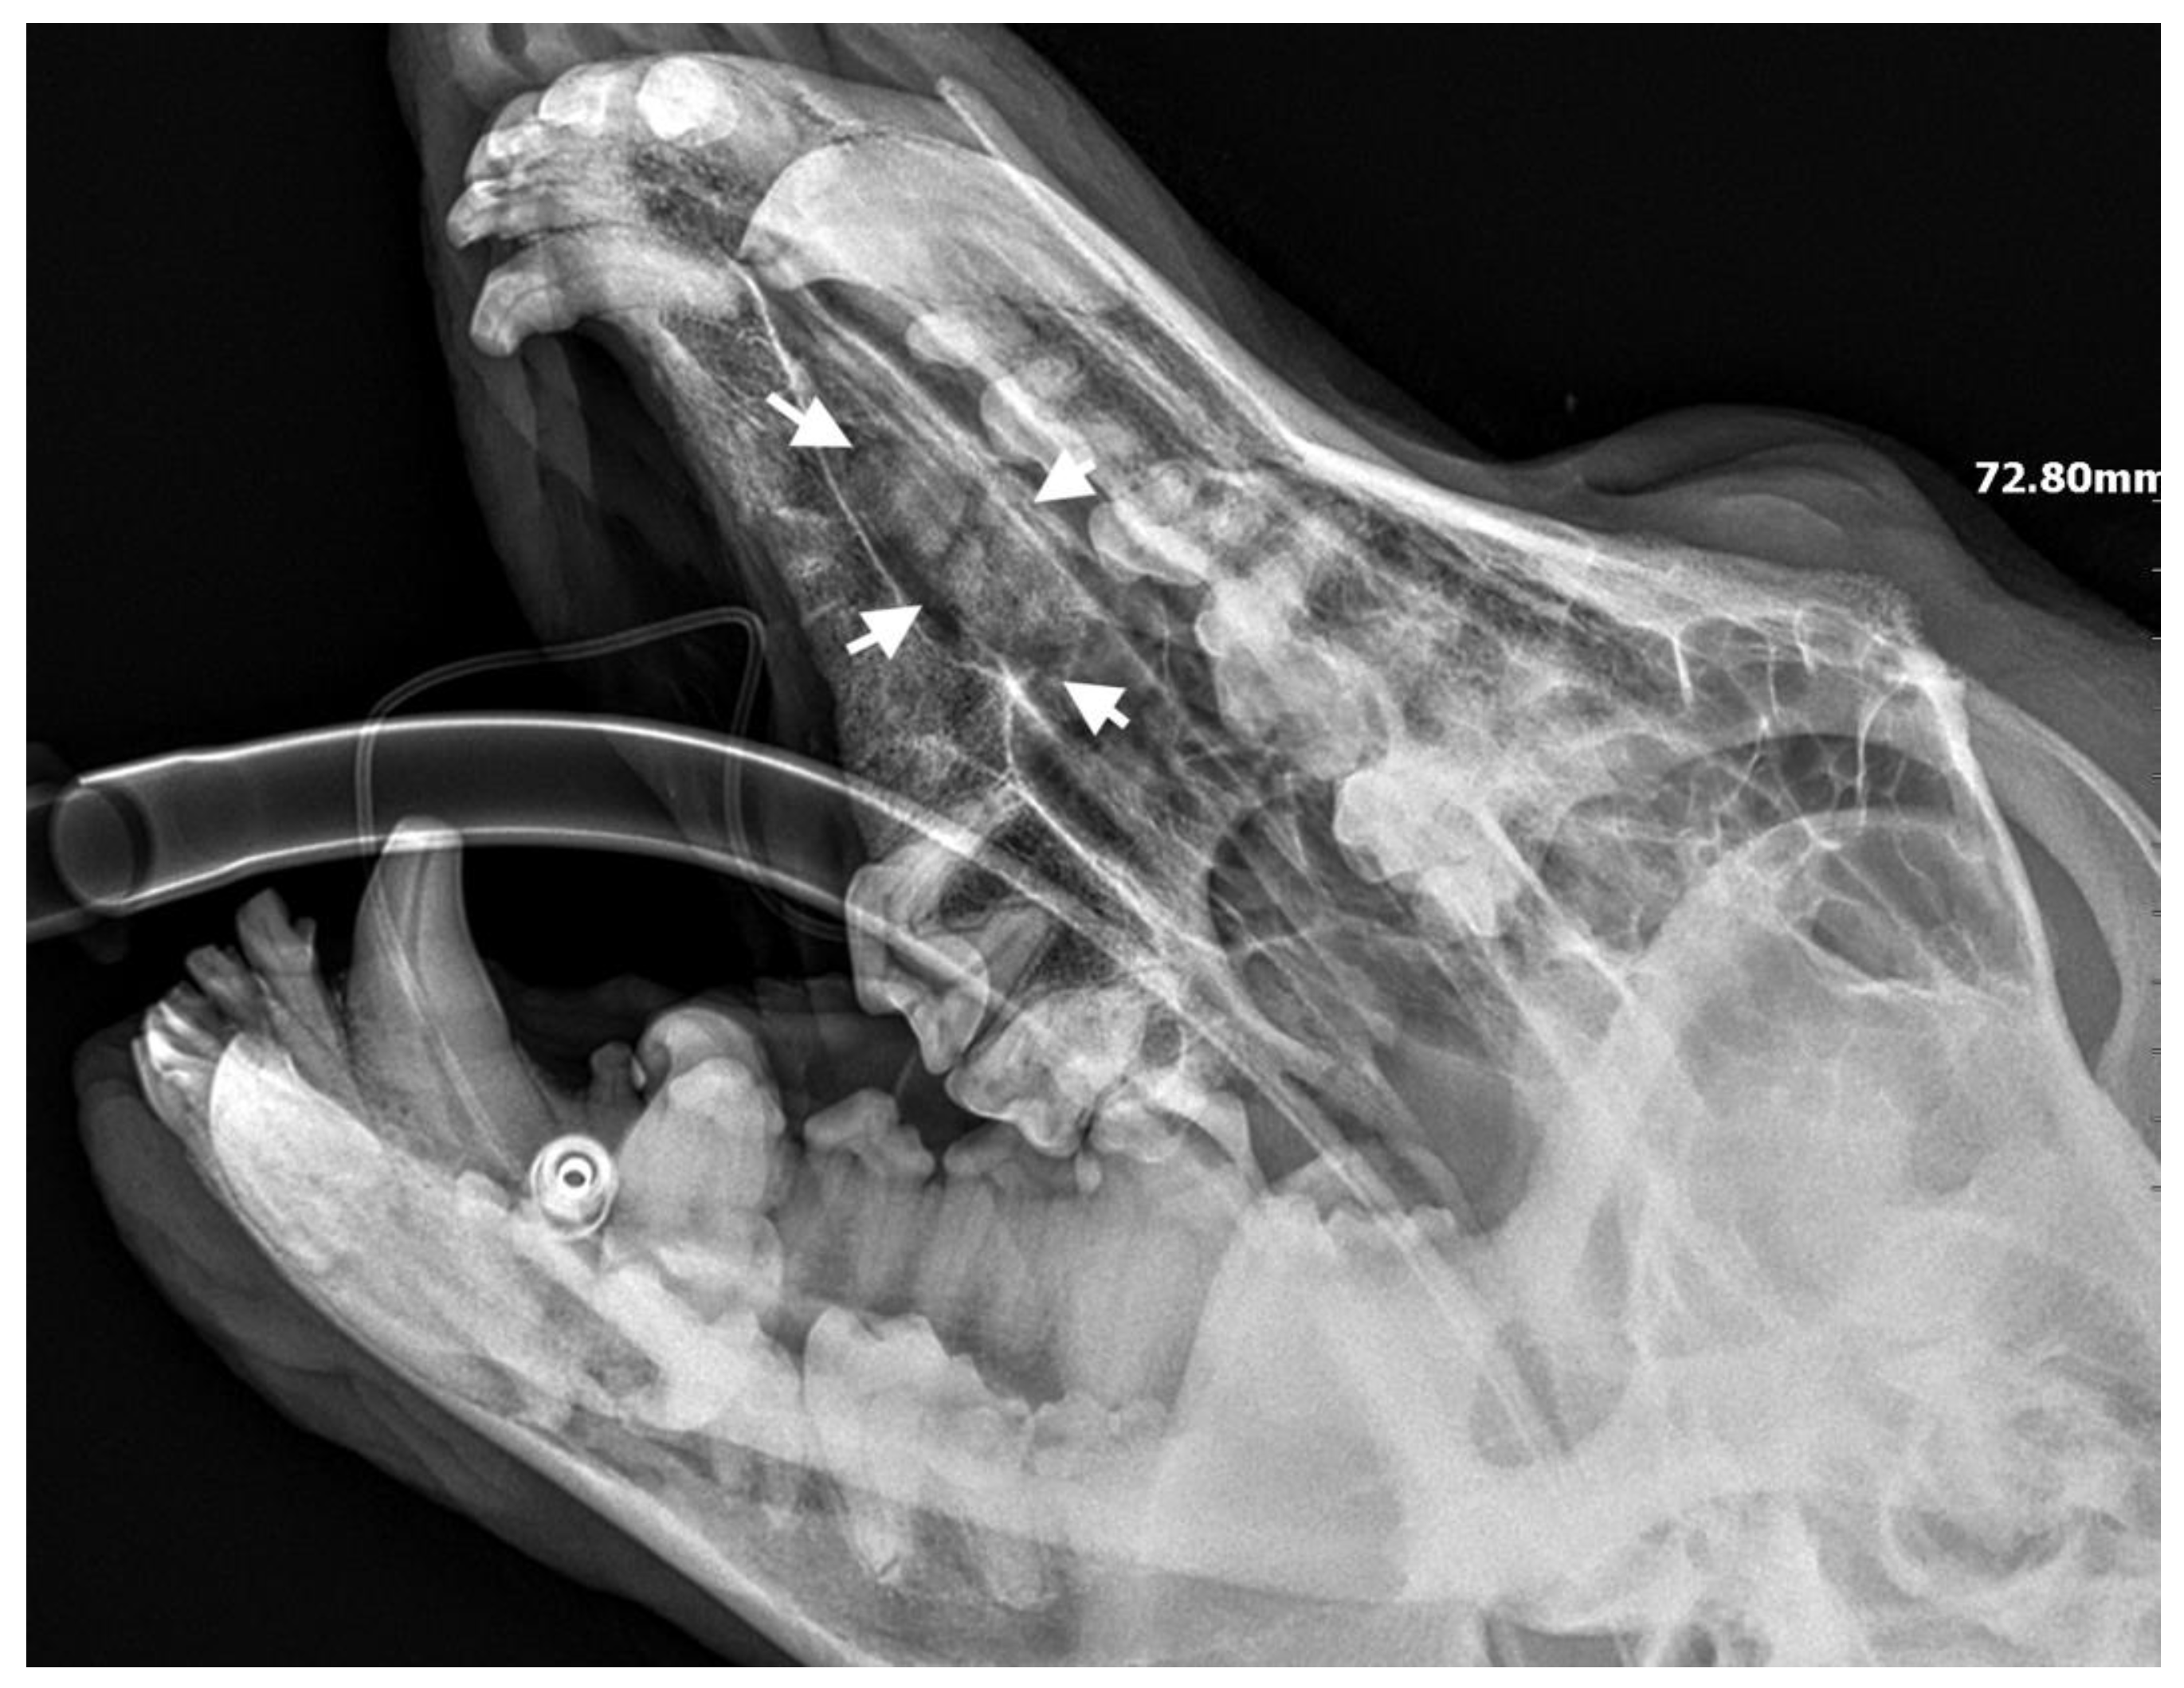

A 7-month-old male Rottweiler was referred for consultation because of severe swelling on the left side of the jaw, with a suspected jaw tumor. Clinical examination revealed no abnormalities in the aforementioned lymph glands and no soreness on palpation. Intraoral examination on the left side revealed severe asymmetry, with enlargement of the facial soft and hard tissues, an absence of permanent teeth, and buccal displacement of deciduous teeth. On the left side, rhinoscopic examination revealed normal anterior nostrils and a left nasal aperture with a lack of patency from the level of the nasal bony inlet to the posterior nostrils. A roentgenogram in the dorsal–ventral projection showed the presence of four ectopic teeth in the maxilla, with the formation of a dentigerous cyst (Figure 2). Using the CLP technique, the ectopic teeth were removed and the cyst walls were lanced. The bone loss caused by the cyst was 7.3 cm × 4.6 cm, and the jawbone left behind was too thin to provide a scaffold for the surrounding tissues and to ensure nasal cavity patency. From a 5 cm pellet of hydroxyapatite polymer material with curdlan previously soaked in saline (according to the manufacturer’s instructions), longitudinal flaps of 5 cm long, 1 cm wide, and 0.1–0.2 cm thick were cut and placed in the bony defect to strengthen the bony scaffolding of the jaw and nasal septum (Figure 3). The gingival flap was sutured with a single suture using 4-0 monofilament material. The first radiological follow-up was performed after 4 weeks, but due to the size of the defect and the size of the pellets of material used, the hydroxyapatite obscured the structures in the nasal cavity, preventing accurate assessment. A rhinoscopic examination revealed patency of the left nasal cavity. It was decided to conduct a radiological follow-up 6 months after the procedure, but the owner, for personal reasons, did not attend the follow-up appointment. After 12 months, another roentgenogram was performed, where a properly healed jawbone with closure of the cyst cavity could be observed. The nasal septum was formed properly, and the resulting bony scaffolding resulted in patency of the left nasal aperture, along with normal airflow on the left side (Figure 4).

Figure 4. Condition 12 months after the surgery to remove ectopic teeth. On the left side, a properly formed jawbone and nasal cavity are shown.